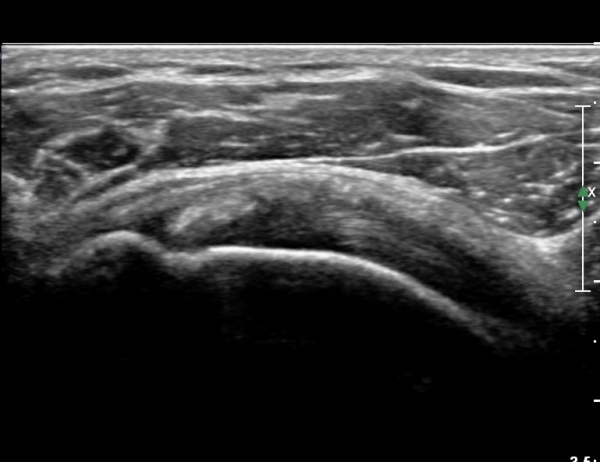

ÃÊÀ½ÆÄ ¼Ò°ß :  È¸Àü±Ù°³°£°Ý(rotato cuff interval) ³»Ãø °Ë»ç»ó  »óºÎ °ß°©Çϱٰǿ¡ ƯÀÌ ¼Ò°ß º¸ÀÌÁö ¾ÊÀ½(»çÁø 1).